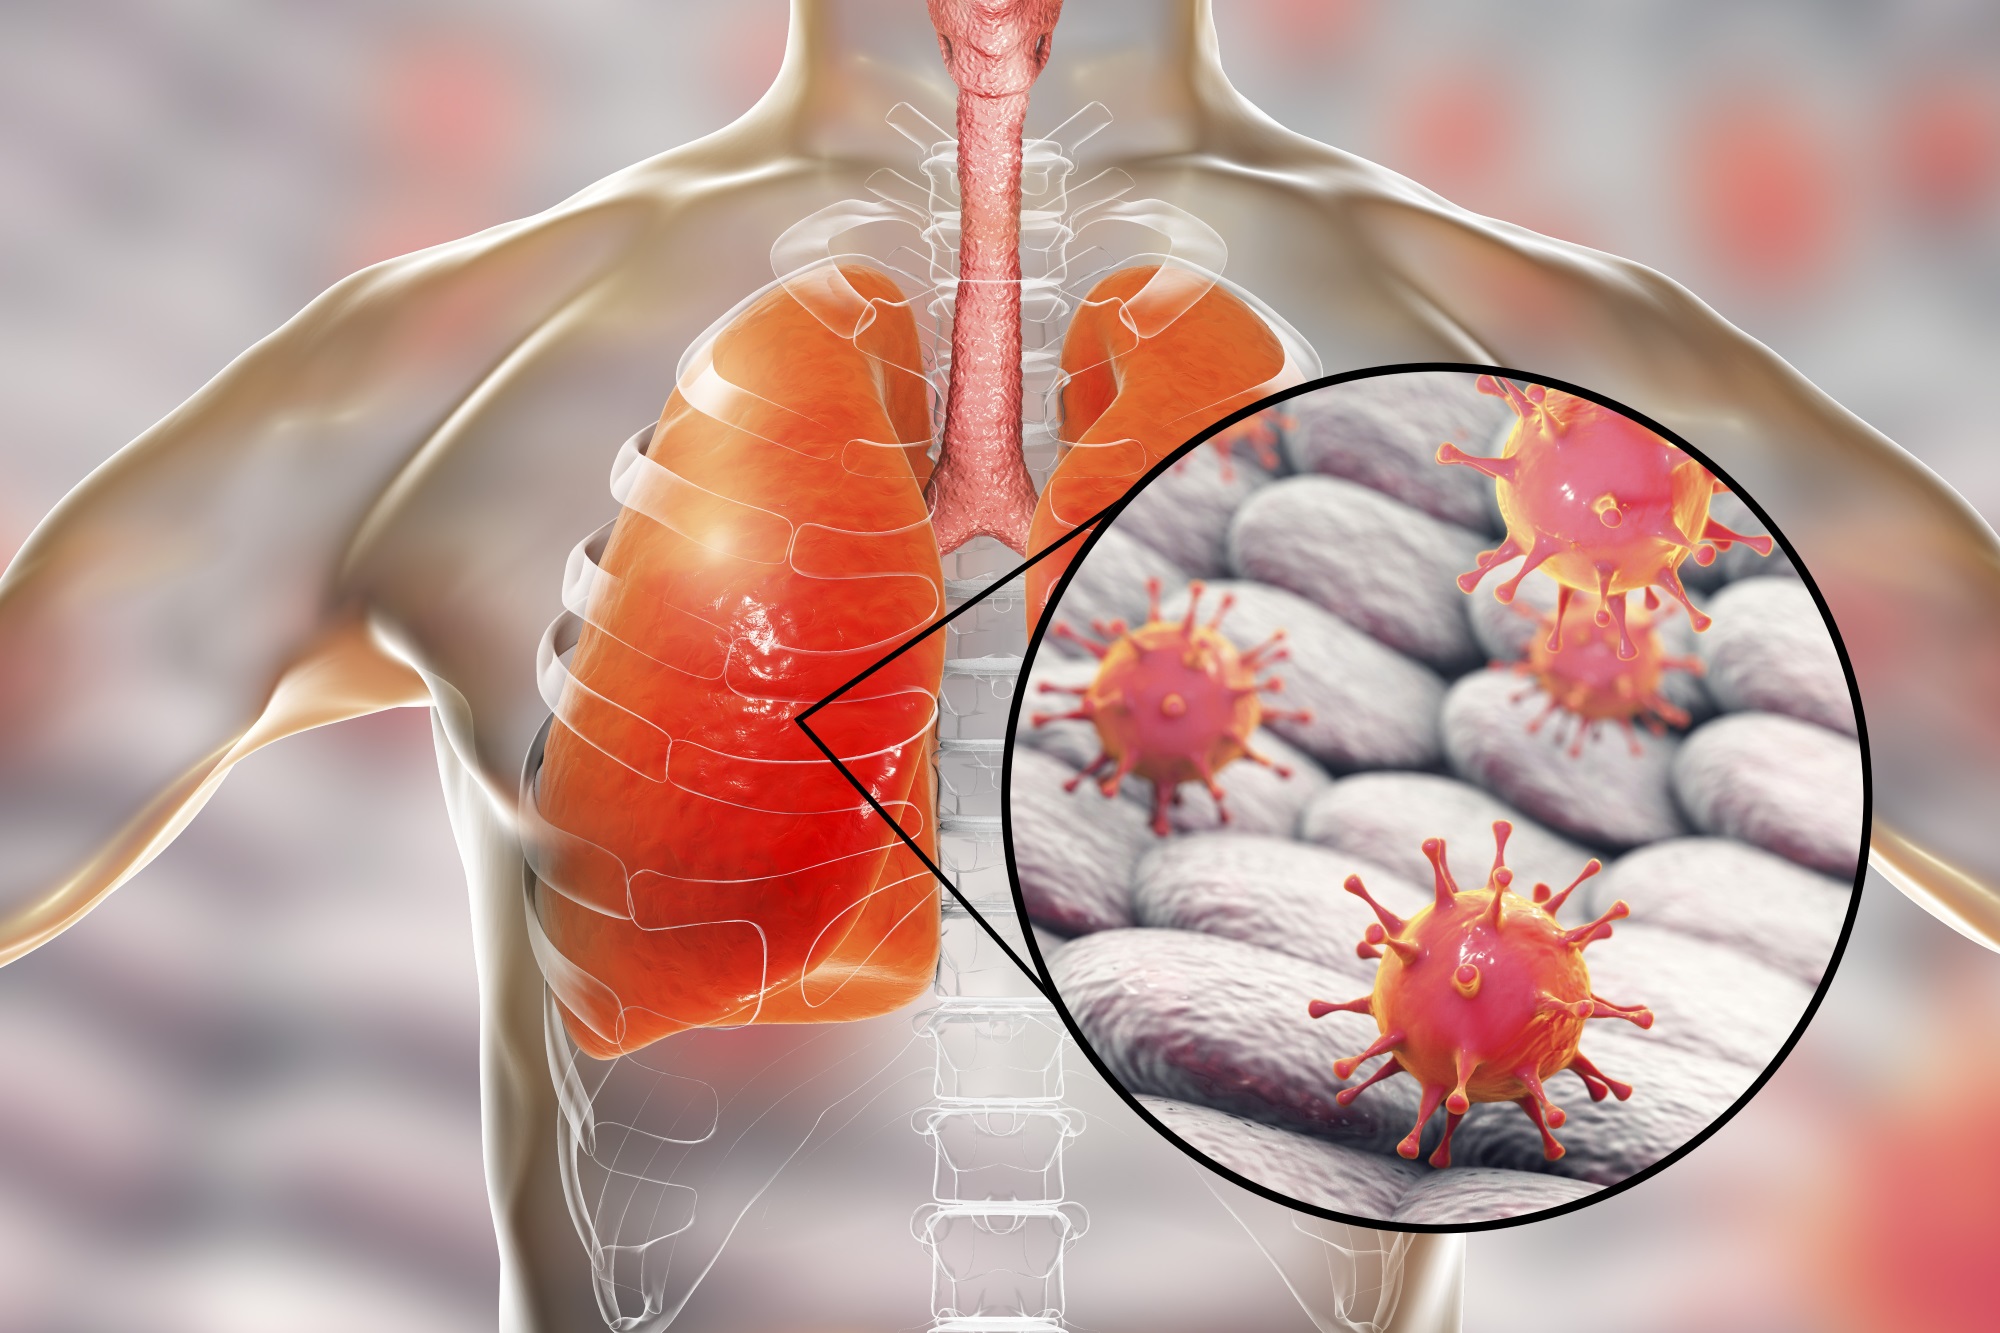

3、预防呼吸道感染:长期卧床易发生坠积性肺炎,截瘫病人呼吸肌麻痹,呼吸活动度小,呼吸道分泌物不易排出,常发生肺部感染,应经常拍背,鼓励咳嗽及作深呼吸,必要时服用祛痰药及做雾化吸入以保持呼吸道通畅。